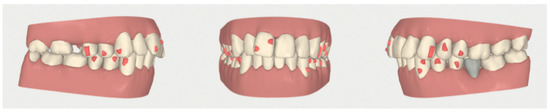

2.2. Orthodontic Planning

2.3.1. Example—Anterior Open-bite

2.3.2. Example 2—Extraction Space Closure